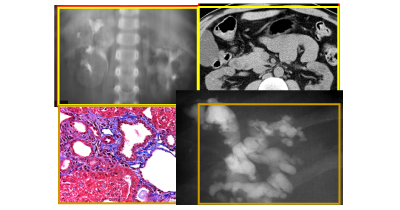

Typical infantile appearance of autosomal recessive polycystic kidney disease.

The kidneys of autosomal recessive polycystic kidney disease (ARPKD) patients surviving the neonatal period often decrease in size and become fibrotic. Late manifestations of ARPKD are often related to hepatic fibrosis and intrahepatic dilatation of bile ducts (Caroli's disease).

Origin of renal cysts in autosomal recessive polycystic kidney disease and autosomal dominant polycystic kidney disease.

Origin of biliary fibrocystic disease in autosomal recessive polycystic kidney disease and autosomal dominant polycystic kidney disease.

Natural history of ADPKD. Renal function remains normal for decades despite unrelenting cystic disease progression.